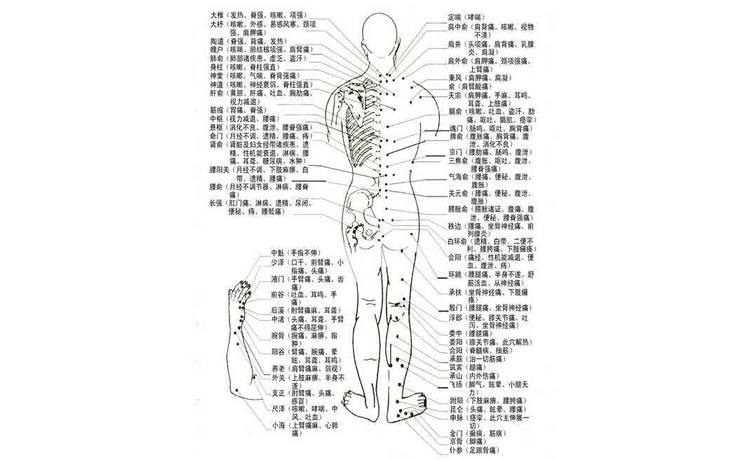

血液净化疗法,清除血液内积存的毒素和病变细胞、自由基、油脂。排除致病因子。可显著促进细胞的新陈代谢,化瘀行气,养血润肤,增强皮肤抵抗力。

调节免疫,重建身体健康生态

血液净化疗法,通过激活免疫细胞,产生一种非特异性脱敏作用,促进白细胞吞噬能力,从而增强机体免疫力,灭菌排毒,重建身体健康的生态环境。

改善代谢,调节机体平衡

血液净化疗法,能够通过减少血液中的红细胞凝聚,提高其携氧能力和改善血流变,增加血液对组织的供氧量,改善机体的代谢状态,使之达到正常的平衡状态。

强化免疫,维护体内环境

血液净化疗法,可激活免疫细胞的正常功能,建立更迅捷的免疫应答模式,还可恢复血细胞滋养功能,减少病变细胞生成,优化内环境,加快皮损修复进程。

安全有效,缩减康复时间

血液净化疗法,具有安全性、有效性和预防性等多重优势,大大缩短了患者康复时间,减轻了患者心理负担。

降低血脂、胆固醇,缓解和预防高血压

控制和降低慢性疾病急性发作的风险

提升肝脏的解毒功能

预防心脑血管疾病

预防癌症发生

治疗和预防过敏发生

预防治疗动脉硬化

预防突发性耳聋

治疗和预防顽固性糖尿病

足部坏疽

外周动脉疾病

自身免疫性疾病

系统性红斑狼疮等

改善各个器官和细胞的功能

延缓和阻碍衰老